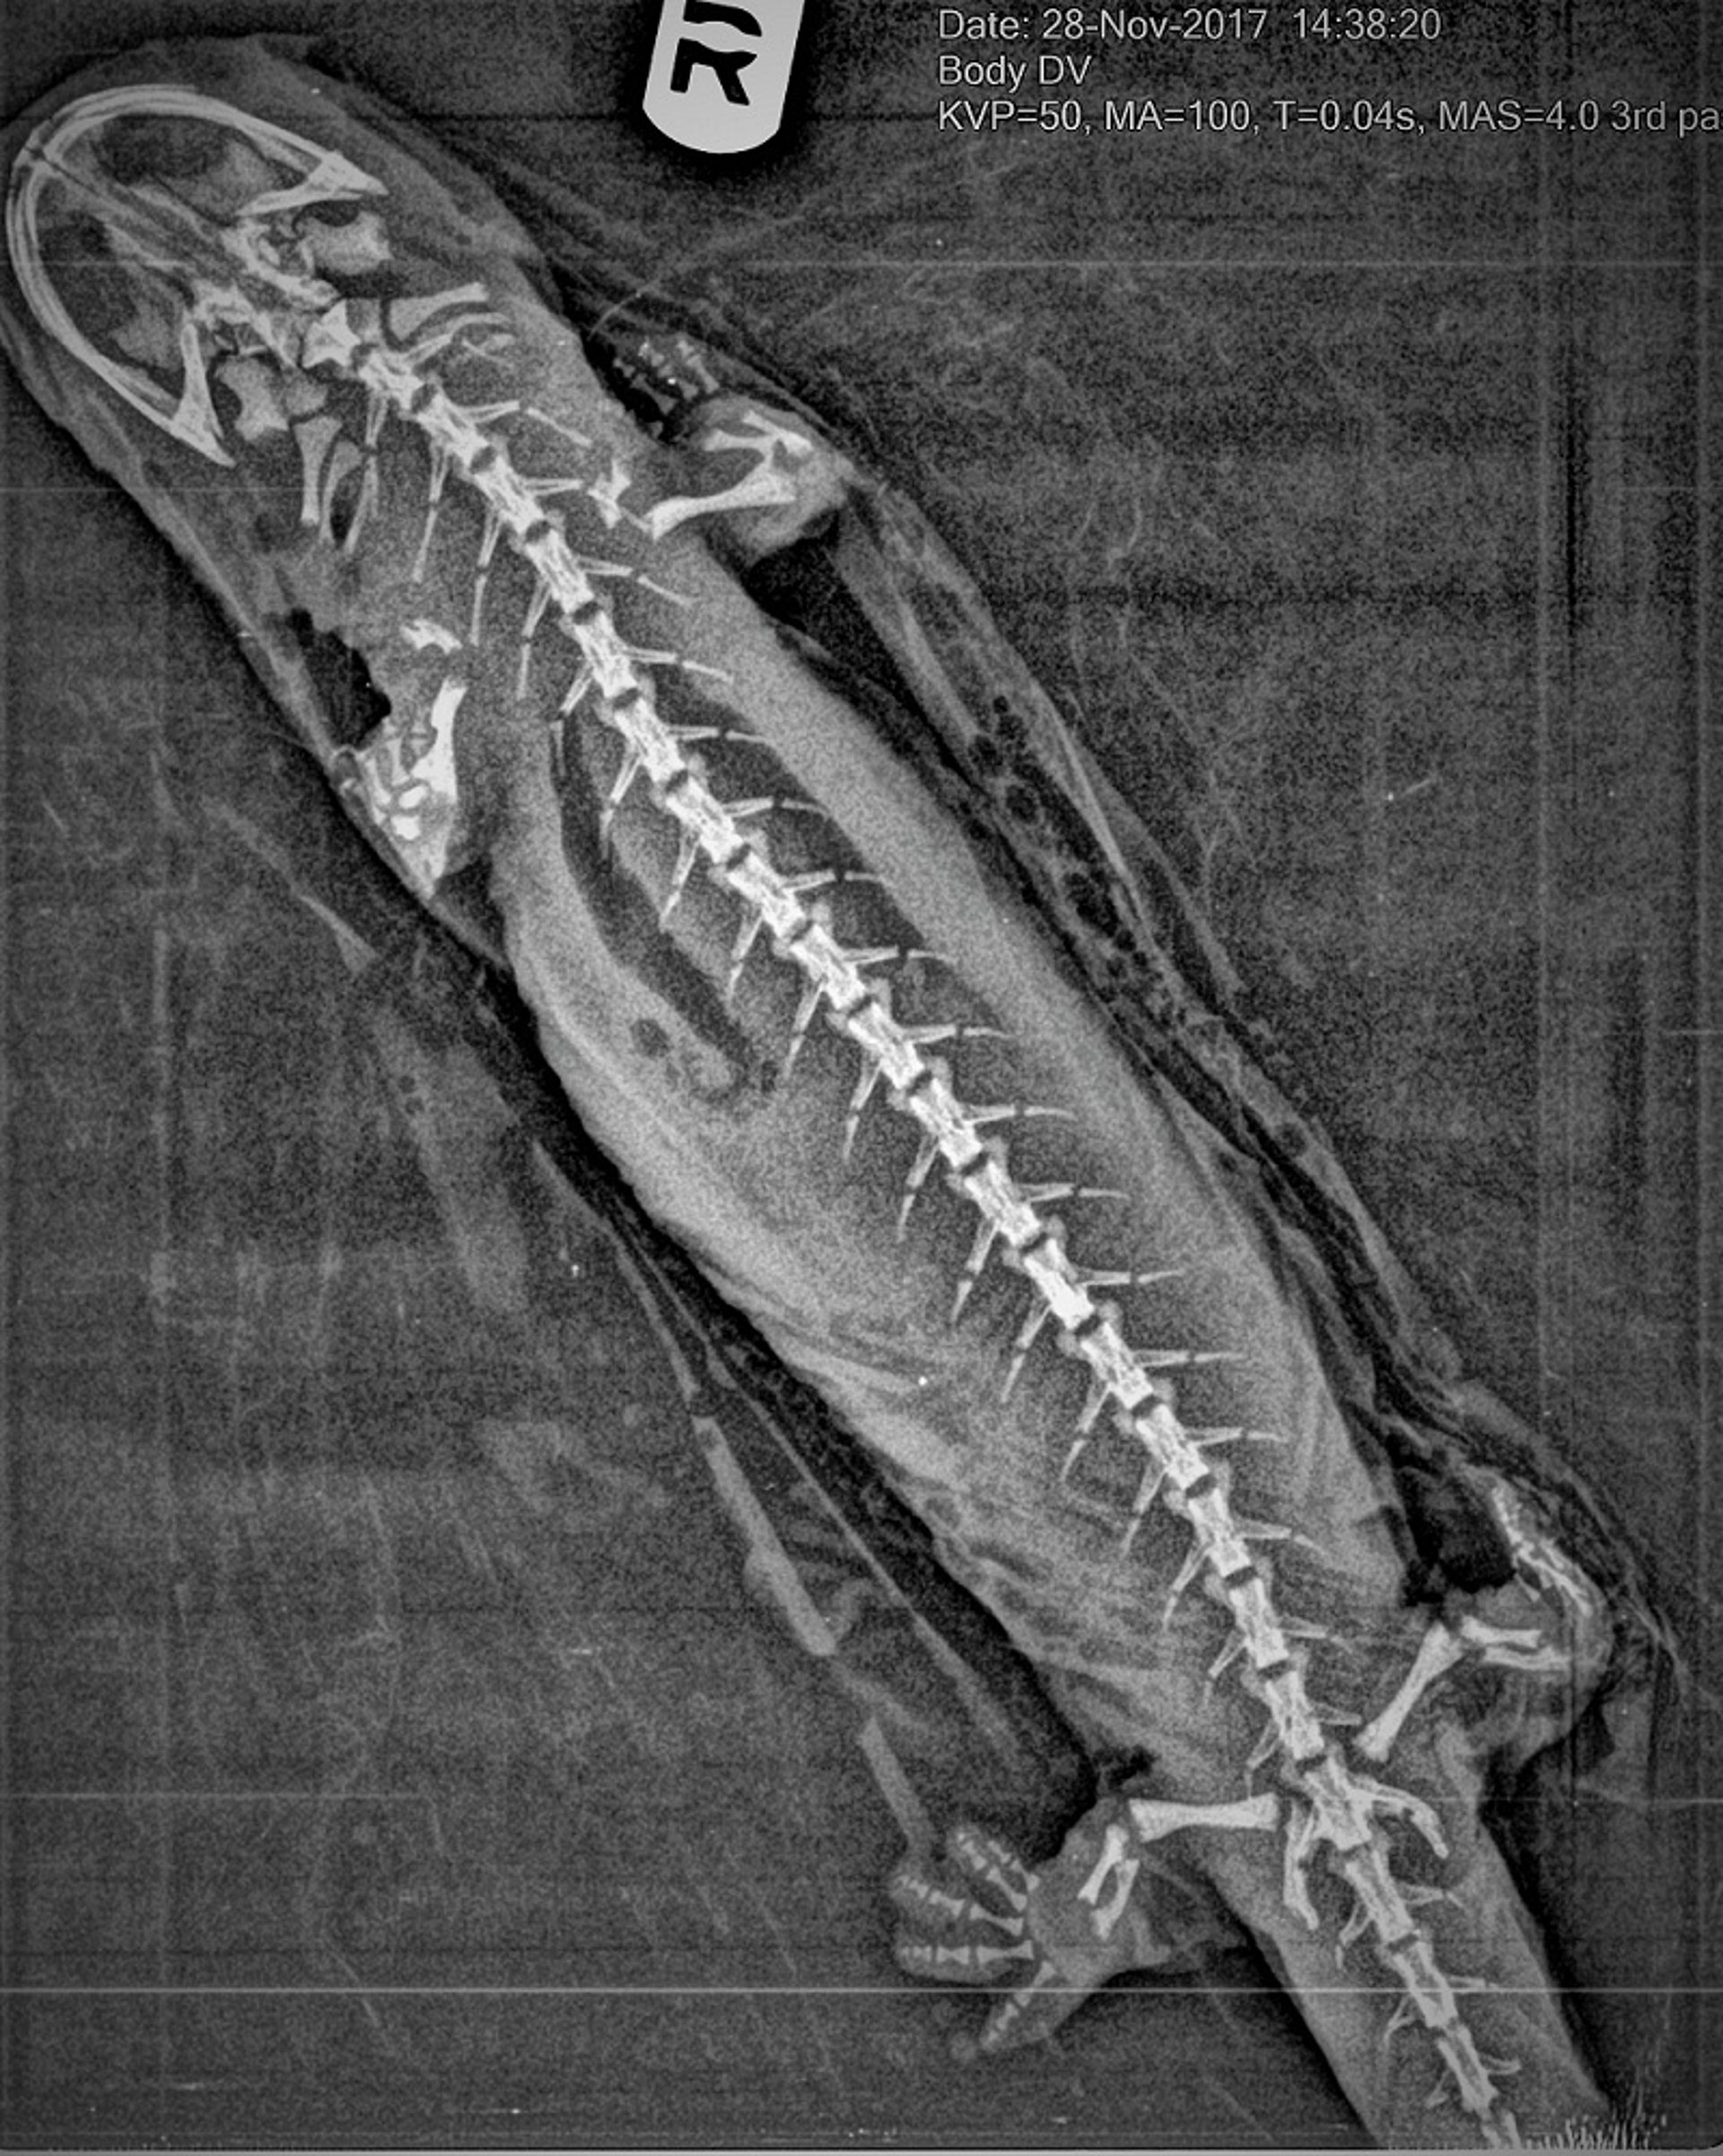

Diagnóstico por imagen, Cryptobranchus alleganiensis

Proyección radiográfica dorsoventral de un adulto de salamandra gigante americana (Cryptobranchus alleganiensis) que muestra una gran cantidad de cartílago presente en los espacios articulares, que a veces se confunde con lesiones metabólicas óseas.

Cortesía del Dr. Taylor Yaw.